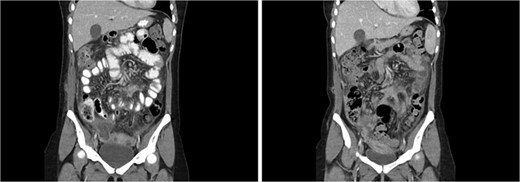

Coronal CT abdomen from admission 3 (left) and admission 4 (right). Heterogenous collection in right pouch of Douglas, progression of mesenteric/omental fat stranding, thickened loops of small bowel.